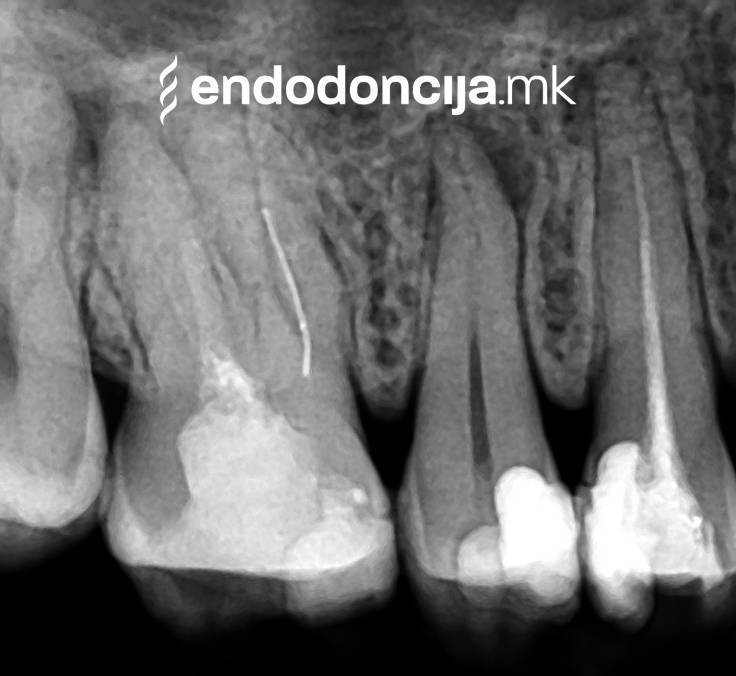

Κατά τη διάρκεια της επεξεργασίας του ριζικού σωλήνα, τα λεπτά όργανα ενδέχεται να σπάσουν. Αυτό μπορεί να αποτελέσει εμπόδιο για την πλήρη προετοιμασία και τον καθαρισμό του ριζικού σωλήνα. Με μια μικροσκοπική επεξεργασία του ριζικού σωλήνα μπορεί να είναι δυνατή η απομάκρυνσή τους υπό ορισμένες συνθήκες, χωρίς να καταστρέφεται η ουσία των δοντιών.

Σε περίπτωση ανανέωσης της θεραπείας του ριζικού καναλιού (αναθεώρηση) παλιά γεμίσματα ρίζας που δεν ήταν επιτυχημένα και ως εκ τούτου ήταν η αιτία φλεγμονών και πόνου, μπορούν να αφαιρεθούν και να ανανεωθούν εξειδικευμένα. Αυτή η θεραπεία εξαλείφει τις φλεγμονές στην περιοχή της ρίζας και καθίσταται δυνατή η πλήρης ανάρρωση.

Εκτός από την ανίχνευση των ριζικών καναλιών, η ενδελεχής προετοιμασία και η απολύμανση του ριζικού σωλήνα είναι η προϋπόθεση για μια επιτυχημένη συνολική θεραπεία. Μέσω της χρήσης των νεότερων οργάνων και αντιβακτηριακών διαλυμάτων, όλα τα υπολείμματα ιστών και τα βακτήρια που υπάρχουν μπορούν να εξαλειφθούν.